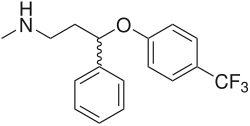

Pharmakologie

Antidepressiva

In der Behandlung von Depressionen besitzen selektive Serotonin-Wiederaufnahmehemmer (SSRI) wie beispielsweise Fluoxetin, Fluvoxamin, Paroxetin, Sertralin und Citalopram einen hohen Stellenwert. Sie sind Hemmstoffe des Serotonintransporters und führen zu einer erhöhten Konzentration und einem verlängerten Verbleib von Serotonin im synaptischen Spalt. Auch die Wirkung der älteren trizyklischen Antidepressiva beruht – zumindest zum Teil – auf einer Hemmung des Serotonintransporters. Die ebenfalls als Antidepressiva genutzten MAO-Hemmer wie Tranylcypromin und Moclobemid verdanken ihre Wirksamkeit einer Hemmung des serotoninabbauenden Enzyms Monoaminooxidase.